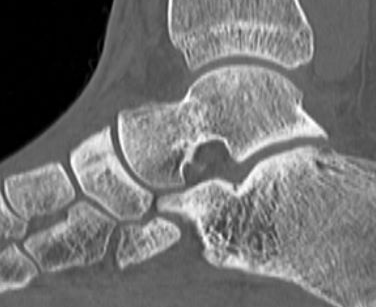

CT

Minimally displaced navicular stress fracture

Displaced navicular stress fracture